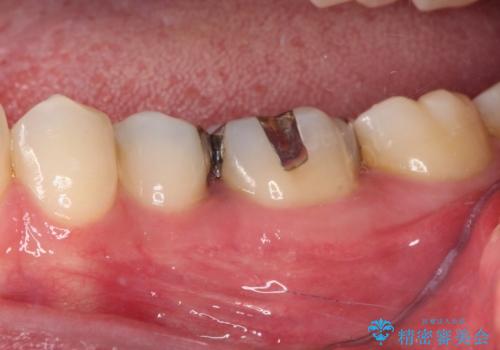

まず麻酔をして銀歯を外し、むし歯を除去し、形を整えて型取りします。

そして次の来院時、セラミックインレーを装着し、噛み合わせなどの調整を行います。

インレーを装着するときは、唾液や血液による接着力の低下を避けるためにラバーダム防湿を行いました。